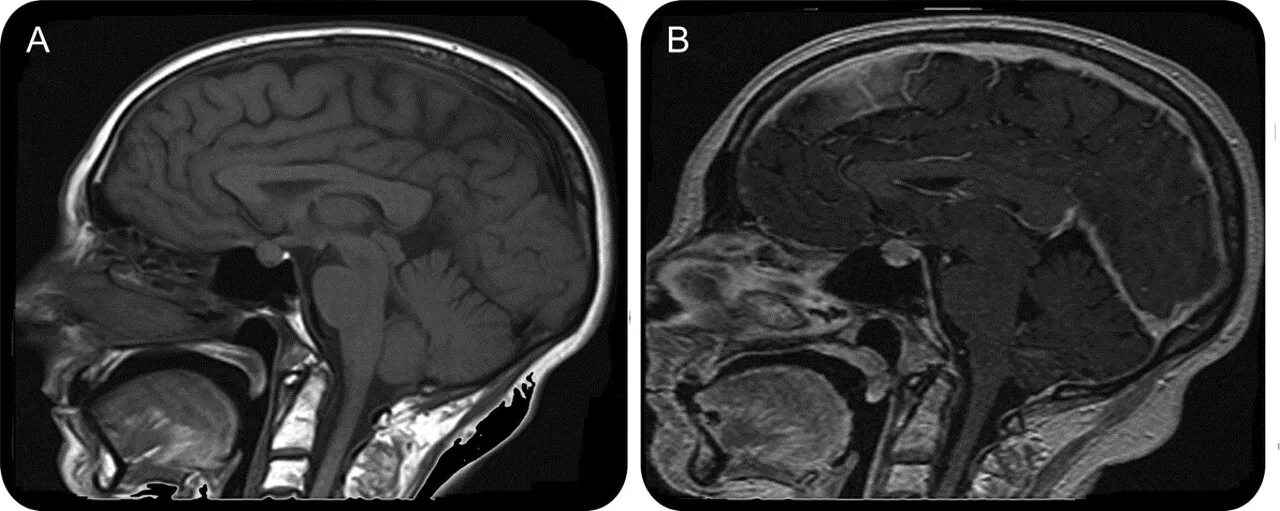

Пролабирование мозжечка